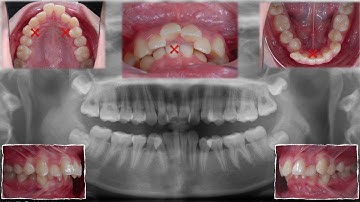

Solving Full cusp Class II with 12mm OJ|【Chris Chang Ortho】CC742